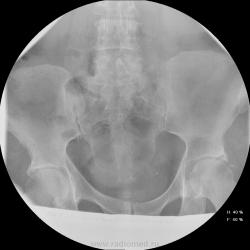

Женщина 55 лет, полная, поступила в неврологическое отделение с жалобами на боли в т.бедренных суставах,  области паха, больше слева. Лечили в поликлинике ДОА, остеохондроз- без эффекта, и направлили в стационар.

Остеохондроз от нижнегрудных позвоночно-двигательных сегментов и ниже, резко выраженный на уровне L5-S1 (3 степень снижения диска). Неполная люмбализация S1 - видны псевдосуставные щели на уровне боковых масс. Аномалия тропизма L5-S1: разноплоскостная ориентация щелей межпозвоночных суставов, один ближе к горизонтальной, второй - ближе к кософронтальной. Гиполордоз. Сколиоз. Деформирующий спондилез. Коксартроз 1 ст. с оссификацией крыш впадин. Флеболит(?!) в малом тазу слева, исключить конкремент в тазавой части левого мочеточника (ОАМ и т.д.; главное - экскреторная урография, желательно с прицельной РГ области мочевого пузыря в левой косой проекции на минуте 15-25).

Ну раз мнений больше нет - Мы заподозрили деструкцию в области тела подвздошной кости над вертлужной впадиной слева и отправили на КТ (обратите внимание на разряжение костной структуры по сравнению с правой стороной). На КТ : множественные очаги деструкции позвонков , больше пострадал остистый отросток L4. Такие же очаги в тазовых костях, наиболее крупный как раз слева над вертлужной впадиной. Левая половина крестца почти полностью разрушена. Кроме этого, очаги в печени, надпочечниках. Тело матки увеличено, в области придатков слева - кистозное образование. После этого посмотрели на наши сникми - почти сразу все увидели, особенно пропажу остистого отростка L4.

Имеем мтс, нужно теперь найти первичный очаг...